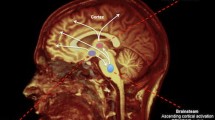

The concept of consciousness has fascinated philosophers, psychologists and neurophysiologists for a long time; however, it remains difficult to give its univocal and universally accepted definition. Consciousness is defined as “the state of full awareness of the self and one’s relationship to the environment”; consequently, a distinction must be made between consciousness (or awareness) and vigilance/alertness (wakefulness). In fact, it is possible for a patient to be conscious, but unresponsive to the examiner, for lack of sensory inputs or for psychiatric reasons. Conversely, a subject can be alert and awake with open eyes, but not conscious and not aware (in part or at all) of itself and of the environment. From a neurophysiological point of view, it has been demonstrated that the brainstem Reticular Activating System (RAS) is responsible for the state of alertness, through its projections to the thalamus and cortex. The integrity of the upper cortical centres, which are closely related to each other and receive the reticular activating stimuli, is also essential for the maintenance of consciousness level. Therefore, Disorders Of Consciousness (DOC) and vigilance may depend on damage to one or both of these neurofunctional systems, acute or chronic, reversible or irreversible. Serious damage to the reticular system, with or without concomitant widespread cortical damage, can produce a state of coma. Coma is then a pathological condition in which the subject lies with eyes closed and he is neither conscious nor alert, with altered - or completely absent - responsiveness to stimuli. In case of widespread damage to the cerebral cortex without involvement of the RAS, a particular condition - named Vegetative State (VS) - may occur: the consciousness of self and of the environment is impaired, but a certain level of vigilance is still preserved. Moreover, there also exist several neurological conditions that can be defined as “borderline”, such as the Minimally Conscious State. Finally, brain death is the irreversible definitive impairment of both the cortical and brainstem functions. Electroencephalography is an important diagnostic and prognostic tool, useful to better characterise the evolution of a coma state, to recognise any kind of epileptiform activity - that could be clinically hidden - and to monitor the effects of antiepileptic drugs, level of sedation, and treatment of intracranial hypertension.

Disorders Of Consciousness (DOC) result from failure of the arousal system. The current knowledge regarding the anatomo-physiology of vigilance dates back to the 1930s and 1940s, owing to the elegant experiments performed by Bremer [1] and Moruzzi and Magoun [2]. Observing cats with their brainstem sectioned between the pons and midbrain and in the lower part of the bulb, Bremer discovered that rostral section caused a clinical state and an EEG similar to that of sleep (with characteristic synchronised EEG sleep rhythms), while animals with caudal section remained awake but with desynchronised EEG rhythms. Many years later, Dempsey and Morrison [3] demonstrated the presence of a system of non-specific projections (independent from specific sensory nuclei) from the thalami to all the cortical regions. This concept was further demonstrated by Moruzzi and Magoun [2], who observed that the electrical stimulation of the medial mesencephalic tegmentum and of the adjacent areas caused the awakening of slightly anesthetised animals, with corresponding EEG desynchronisation as in normal awakening, in response to sensory stimuli. The sites that induced awakening upon stimulation consisted of a series of neuronal stations extending from the non-specific nuclei of the medial thalamus to the caudal midbrain. These areas corresponded to the complex system of the ascending reticular formation, a system that is widely innervated by axon collaterals of the ascending sensory systems and is, therefore, in a state of tonic activation. Moreover, since this region, in particular the medial thalamus, projected widely to the cerebral hemispheres, the concept of a Reticular Activating System (RAS) that maintained the waking state originated, which inactivation led to a state of unconsciousness. Despite several experimental disagreements [4], the paramedian upper mesencephalic tegmentum and the lower diencephalon began to be considered as the brain system responsible for arousal. The anatomical boundaries of RAS in the upper midbrain are indistinct, since it is scattered throughout the paramedian regions of the rostral part of the pons and of the mesencephalic tegmentum. In the thalamus, RAS includes the posterior, paramedian, parafascicular and medial portions of the centromedian and intralaminar nuclei. In the brainstem, RAS includes the nuclei of the reticular formation, which receive collaterals from the spinal and trigeminal-thalamic pathways and project widely to the entire cortex, and other key structures for arousal, including the raphe nuclei, locus coeruleus, substantia nigra pars compacta, ventral tegmental area and the mesopontine tegmentum, the latter including the pedunculopontine and laterodorsal tegmental nuclei. These nuclei extend throughout the brainstem, sending ascending and descending signals to influence arousal. Furthermore, their dendrites are positioned in the brainstem such as to detect signals that pass to and from the periphery. The dendrites of these neurons form web-like “reticula” around the passing axons and they can detect a wide variety of external sensory or internal thalamic stimuli passing through the surrounding structures. Therefore, these reticular neurons are positioned strategically to respond to both external and internal signals in the control of arousal [5, 6] (Table 46.1).

The sensory stimulation has therefore a double effect; conveying information from somatic structures to the cortex and activating the regions of the central nervous system on which consciousness depends. Moreover, the cortex does not limit to receiving stimuli from the RAS, but also modulates these input information through corticofugal projections towards the reticular formation.